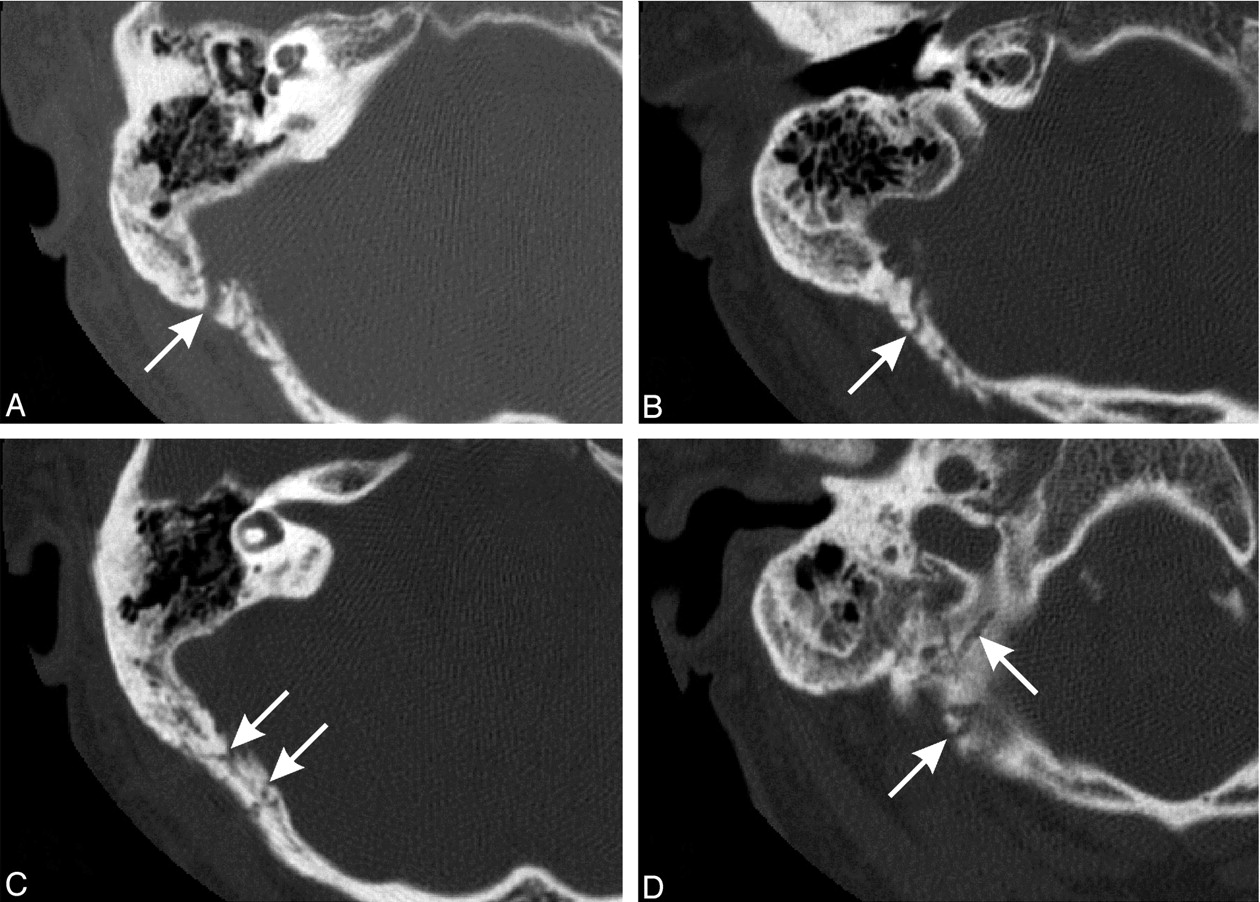

Axial CT images (1-mm helical sections) through the right petrous temporal bone demonstrating the transcalvarial channels (arrows). Note resolved otomastoiditis (images superior to inferior).

A 66-year-old man with a history of type II diabetes presented with bilateral otitis externa secondary to Aspergillus niger. Because the right side failed to resolve, the patient was scanned with CT (Fig 1), which demonstrated fluid within the middle ear cleft, as well as opacified and poorly pneumatized mastoid air cells, possibly representing chronic otitis media and mastoiditis. Three months later the patient developed right-sided pulsatile tinnitus, with a clinically palpable right occipital artery. Cessation of the patient’s symptoms followed digital compression of this vessel and on turning his head to the ipsilateral side. A bruit was auscultated over this region. Further CT imaging (Fig 2) was noteworthy for the near resolution of the right-sided otomastoid findings and the new onset of multiple linear bony defects traversing both tables of the adjacent right occiput, consistent with a dural arteriovenous fistula.